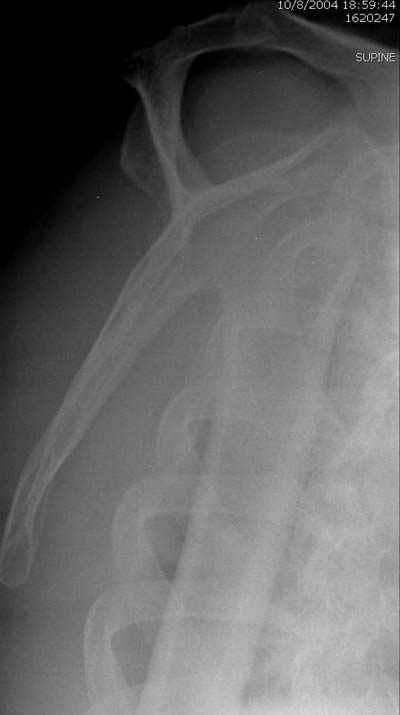

Женя, а как ты водишь спицы, в смысле, как делаешь входное отверстие, и как в него проводишь V-спицу? А то о дна из спиц, та, у которой не дошла до головки одна палочка буквы V, как-то выглядит на рентгенограмме, как будто или через очень большое отверстие введена, или каждая половинка через отдельные отверстия.

В чем ты видишь причину вторичного смещения?

Мне кажется, проблема в том, что не все концы спиц зашли в головку, и зашедшие - недостаточно далеко прошли.

Спицы провожу по передней и задней поверхностям плечевой кости через 4,5 мм отверстия на разных уровнях.

Идеей презентации случая была демонстрация важности постоп Рг - хотя казалось бы все было сделано под флюороскопическим контролем и интраоперационно подозрений на нестабильность не возникло, а такая вот

неожиданность...

V-спица проводится через 4,5 мм отверстие. Видимо, из-за разной длины вторая половина спицы *пролетела* мимо отверстия, что и привело к вторичному смещению костных фрагментов.